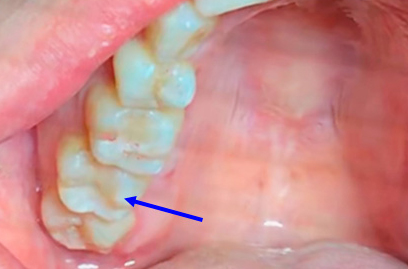

奥歯のジルコニア

| 年齢・性別 | 22歳・男性 |

|---|---|

| 主訴・治療部位 | 他院で虫歯治療 詰め物の治療が必要と判断を受けたが、自費診療の費用が高価で治療を断念 インターネットで当院を知りご来院 右上6番、右上4番 |

| 治療費用 | 合計:88,000円 ジルコニア:44,000円×2 (2023年1月現在) |

| 治療期間 | 約1ヵ月 |

| 治療内容 | 虫歯を除去し、型をとりました。 神経の近くまで虫歯になっていたため、神経の保護処置も行いました。 |

| リスク・副作用 | 虫歯が進行し、神経の治療になる可能性があります。 神経の近くまで削っているため、治療直後は敏感になり痛みが出る可能性があります。 かみ合わせの強い方は詰め物が取れてしまう可能性があります。 |

| 治療方針 | 治療必要な箇所は終了 親知らずは埋まっているが、痛みや腫れはないため、定期検診にて経過観察していきます。 |

| 担当者所見 | 歯周病検査は異常なし 虫歯リスクを下げるため、歯ブラシの他にフロスや歯間ブラシの併用を提案しました。 |